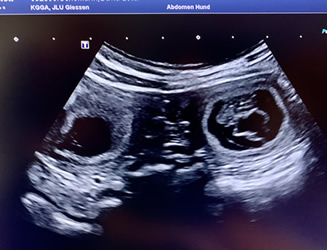

22. Mai 2024: Juchhu, Layla ist trächtig

Heute Vormittag haben wir in der Uniklinik Gießen beim Ultraschall mehrere Fruchtanlagen erkennen können und sind überglücklich, dass es geklappt hat!

Ganz lieben Dank an alle, die uns die Daumen gedrückt haben!

Bitte weiterhin Daumen drücken, dass auch die restliche Trächtigkeit problemlos über die Bühne geht und die Welpen Ende Juni gesund und munter das Licht der Welt erblicken!